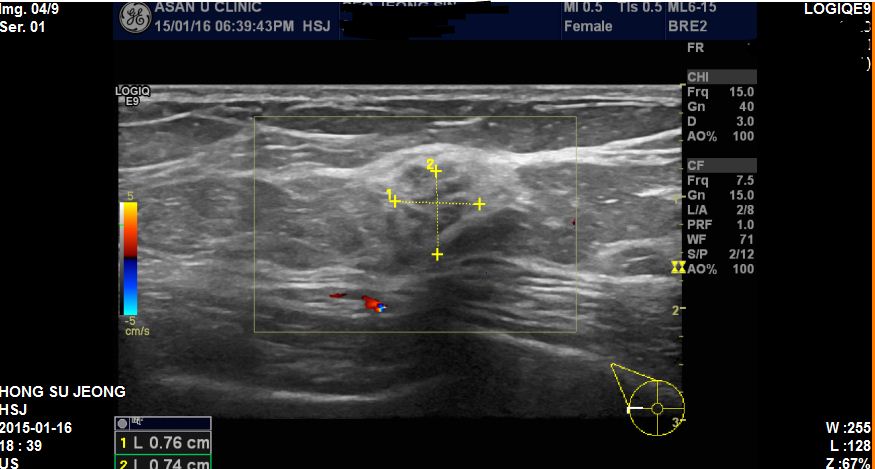

외부 유방촬영에서 우측유방에 이상소견으로 내원하신 56세 환자분이십니다.

본원에서 부분초음파 진행후 우측 9시방향에 0.8cm의 혹 조직검사 시행하였고

침윤성 유방암 진단되었습니다.